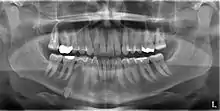

An impacted tooth is one that fails to erupt into the dental arch within the expected developmental window. Because impacted teeth do not erupt, they are retained throughout the individual's lifetime unless extracted or exposed surgically. Teeth may become impacted because of adjacent teeth, dense overlying bone, excessive soft tissue or a genetic abnormality. Most often, the cause of impaction is inadequate arch length and space in which to erupt. That is the total length of the alveolar arch is smaller than the tooth arch (the combined mesiodistal width of each tooth). The wisdom teeth (third molars) are frequently impacted because they are the last teeth to erupt in the oral cavity. Mandibular third molars are more commonly impacted than their maxillary counterparts.

Classifications enable the oral surgeon to determine the difficulty in removal of the impacted tooth. [9] The primary factor determining the difficulty is accessibility, which is determined by adjacent teeth or other structures that impair access or delivery pathway. The majority of classification schemes are based on analysis on a radiograph. The most frequently considered factors are discussed below.

Angulation of tooth

Most commonly used classification system with respect to treatment planning. Depending on the angulation the tooth might be classified as:

Relationship of tooth to anterior border of ramus

This type of classification is based on the amount of impacted tooth that is covered with the mandibular ramus. It is known as the Pell and Gregory classification, classes 1, 2, and 3.[10]

Relationship of tooth to occlusal plane

The depth of the impacted tooth in relation to the adjacent second molar serves as the foundation for this type of classification. This was also given by Pell and Gregory and is known as the Pell and Gregory A, B, and C classification. Relationship to the occlusal plane A-C classes